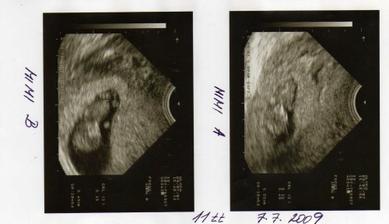

10.6. - první oficiální UTZ v CARu- 2 srdíčka, uvidíme, jak se poperou

20.7. Prediko Zlín, screeining v 1.trimestru- vše OK,miminka s sebou mrskala jak splašená 🙂, no hold celý tatínek.....